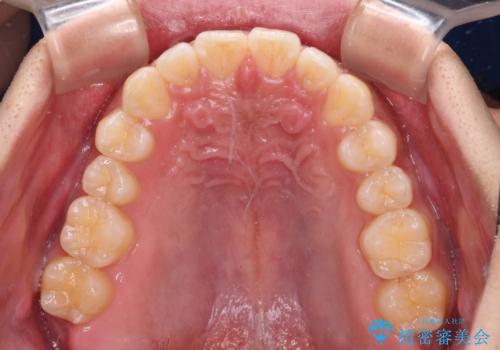

デコボコとディープバイトを治したい インビザラインによる矯正治療

- 前歯のデコボコや隙間と深い咬み合わせ(ディープバイト)を気にして来院された患者様です。

インビザラインによる上下歯列の側方拡大と後方移動、IPR(歯と歯の間を削る)にるスペースの獲得により、デコボコとディープバイトを改善することとしました。

気になっていたデコボコや隙間は改善し、きれいな歯列に整えることができました。

咬合力が非常に強い方であったため、これ以上のディープバイトの改善は困難となりました。